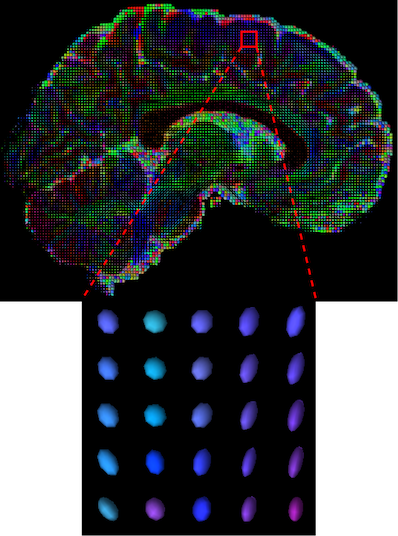

Diffusion Weighted Imaging (DWI) is a non-invasive magnetic resonance imaging (MRI) modality developed to monitor water diffusivity and reveal the micro-structure of the human body [1]. While conventional structural MRI sequences (e.g. T1, T2) provide information about the general morphological information of the brain, DWI provides additional information regarding brain dynamics with water diffusivity as a proxy. This set of sequences acquired with different gradient directions can then be summarised using a Diffusion Tensor Imaging (DTI) model to uncover microstructural information. Based on the fact that different tissues have different diffusion properties, the DTI model explains the directionality of the water diffusivity and its corresponding quantitative anisotropy [2]. The diffusion of a particular voxel can be characterized as an ellipsoid (Figure 1(a)) that can be mathematically formulated as a symmetric tensor matrix (Figure 1(b)). The coordinate system is typically aligned with the main magnetic field and body of the patient. Since the relationship between two principal directions is theoretically symmetric, i.e., , and , only 6 unique coefficients are needed to construct the tensor at a particular voxel.

The visualization of inpainted results (showing the whole diffusion tensor for each voxel) generated from different models are demonstrated in Figure 3, where the tensor is represented in RGB coding that colours red, green and blue represent diffusion in the x, y, and z axes respectively. One typical example of reconstruction in the disrupted ROIs has been zoomed for visualization. Compared to the ground truth, TW-BAG is able to generate more distinct orientations following the original distribution and intensity across sagittal, coronal and axial views, which could demonstrate water diffusivity (denoted by eigenvalues of tensor model) more accurately. As indicated in Figure 4, the boundaries and textures of the FA map for TW-BAG are less blurry than the other competing models, validating the effectiveness of TW-BAG from a neuroscience perspective.